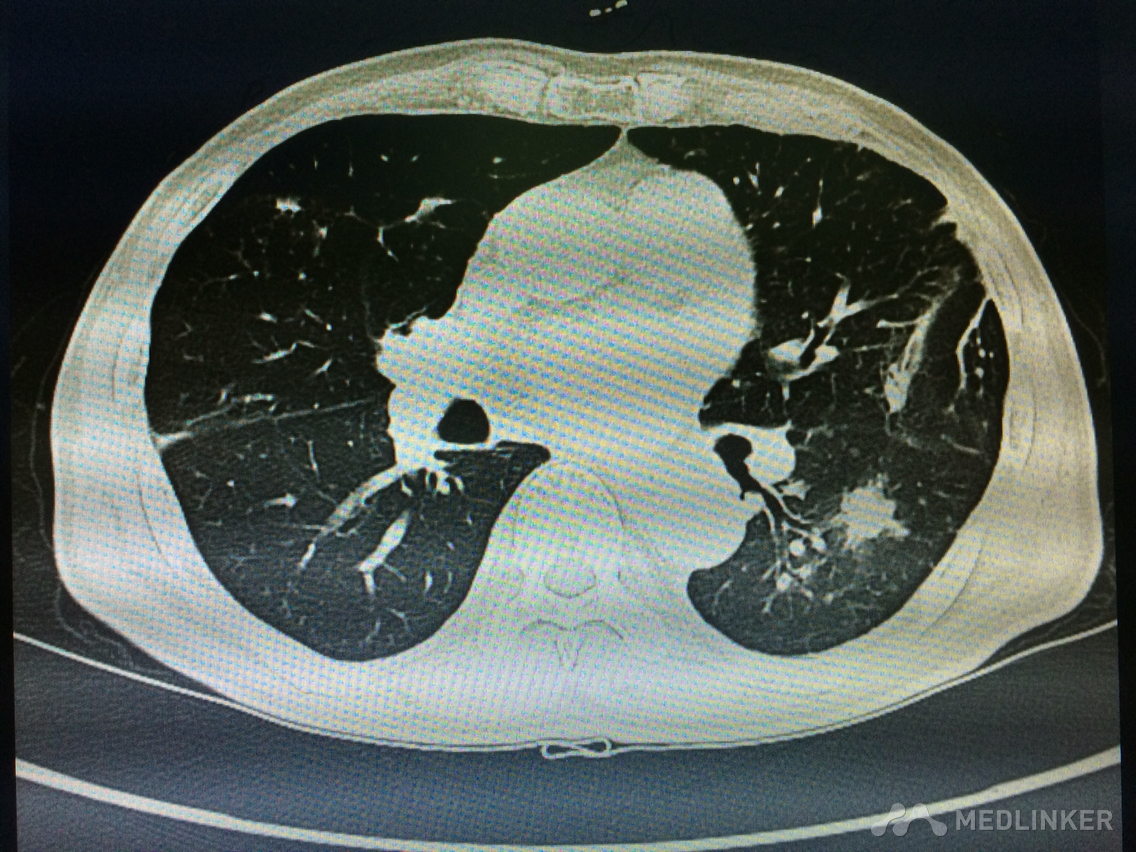

看这胸部CT?

咳嗽咳痰发热3天,伴胸痛气紧,偶痰中带血,体温38.7,伴全身乏力。